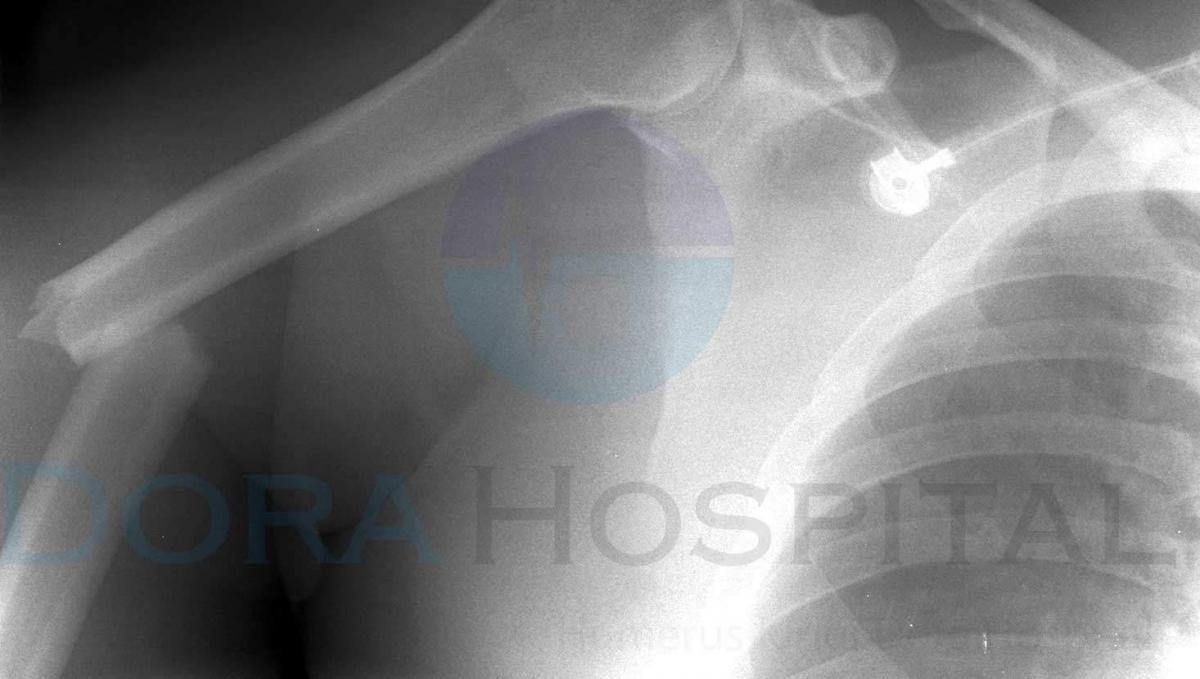

Sorunlar yer almaktadır. Humerus kırkları X – ray ile rahatlıkla teşhis edilebilir. Alçı, atel veya breys gibi tedavi yöntemleri kullanılarak iyileşme sağlanabilir. Hasarın boyutları ve hasta durumuna göre farklı türden tedaviler de uygulanabilir. Bu sorun, top fırlatma, gülle atma, bilek güreşi vb. faaliyetlerde ortaya çıkabilir.